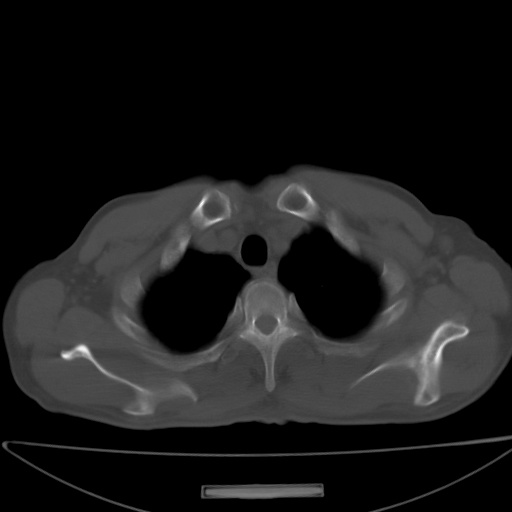

以下是引用jsgdoctor在2008-11-6 22:12:00的发言:[br]右主支气管壁明显增厚,管腔狭窄.考虑为右侧中央型肺癌伴阻塞性炎症\\肺脓肿.

以下是引用zjzjr在2008-11-6 20:25:00的发言:[br]中心型肺ca,合并阻塞性肺炎

以下是引用zsl6918在2008-11-6 19:43:00的发言:[br]右侧中心性肺癌(鳞癌)